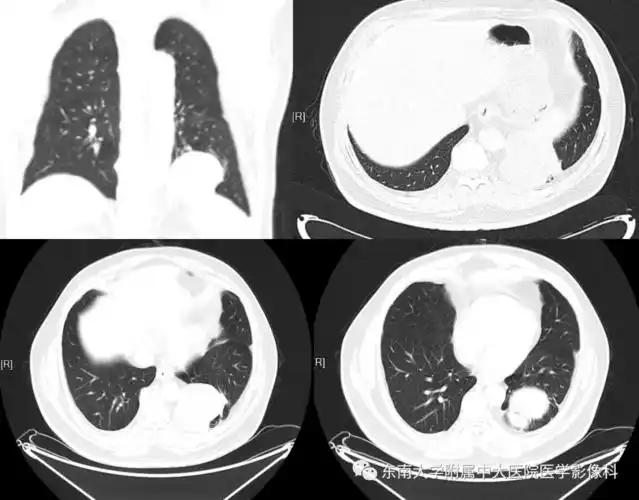

肺隔离症影像表现_郑孝飞

肺隔离症

肺隔离症诊断之影像与病理